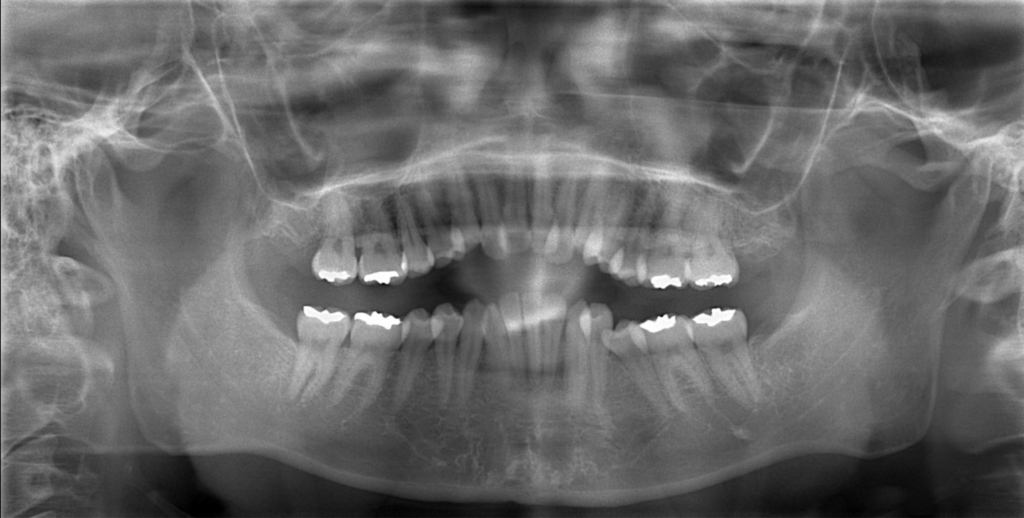

レントゲン写真で確認すると、

この患者さんの場合、

【抜歯】

上下の左右の奥歯を1本ずつ計4本抜歯(4番目の奥歯を抜きました)

レントゲン写真でも矯正治療前後を比較してみましょう